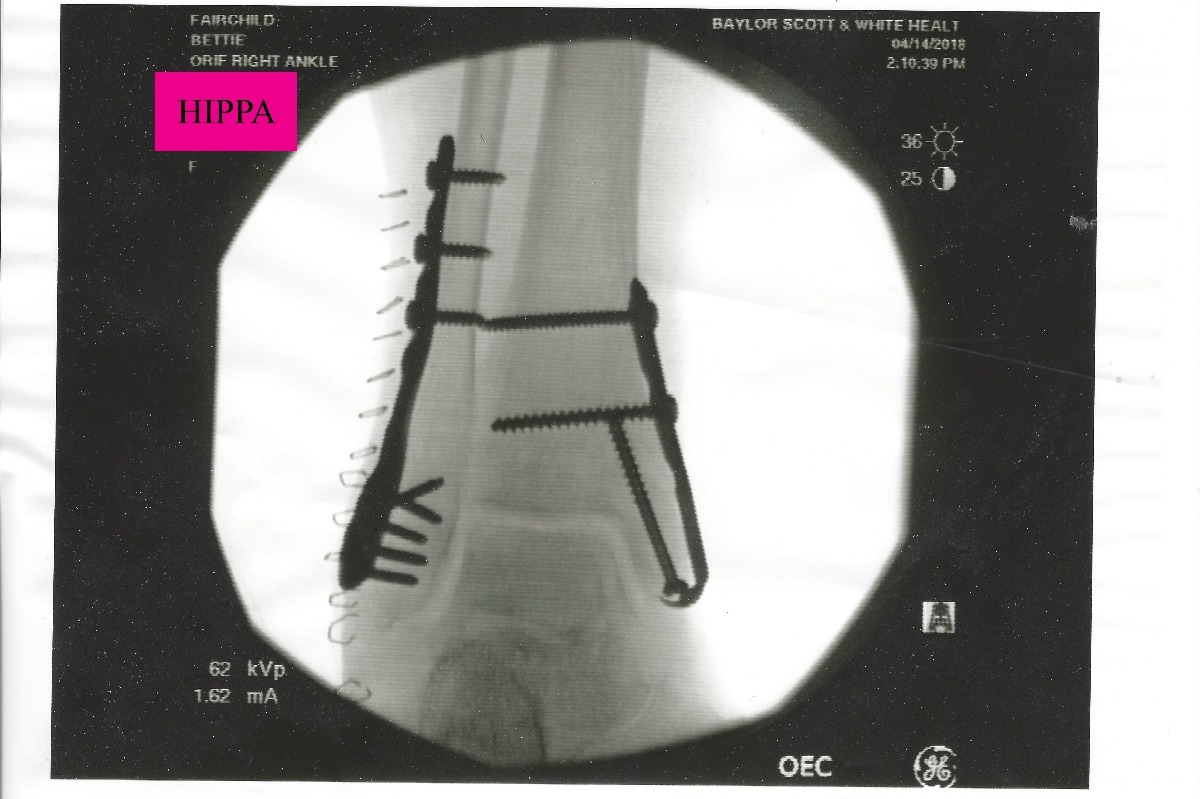

However, the move has not been as smooth as they would have liked. In February, Bettie was hospitalized for an infection and had to go to rehab to regain her strength. On April 12th, Bettie fell in her bathroom and broke her right ankle in 4 places as well as dislocating it. The break was a compound fracture and she needed emergency surgery (Photos Below).